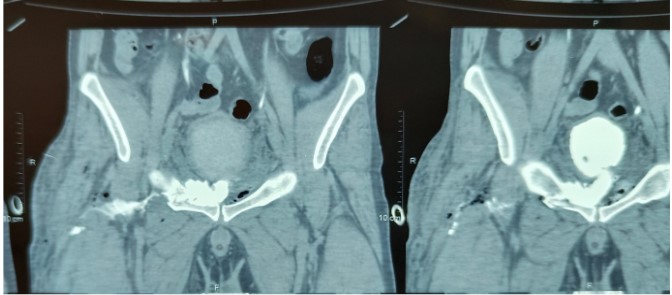

Our index case is a 28-year-old male who fell from a height of approximately 2 stories resulting in a closed pelvic fracture. The patient presented to us within 12 hours of injury with a right thigh wound caused by a penetrating injury caused by a metal rod. On presentation, he had an approximately 2 cm by 2.5 cm lacerated wound over the lateral aspect of the right thigh with a serous fluid like discharge from the wound site. On foley’s catheterisation, 400 millilitres of clear urine was drained. Ultrasound revealed normal kidneys bilaterally with a partially distended bladder as well as peri vesical collection. Computed tomography (CT) scan revealed right pubic ramus fracture with multiple displaced fragments as well as a left acetabular fracture. On delayed phase, contrast extravasation was noted on the right side of the bladder neck via a defect measuring 10 mm x 15 mm. The contrast was seen extending along the space of Retzius as well as along ilio-psoas and obturator internus muscles as well as soft tissue spaces of the thigh. After 3 days of conservation and drainage via catheter, a diagnostic cystoscopy was performed and revealed a zone of erythema at the left superolateral surface of the bladder approximately 2 cm from the bladder neck. However, no obvious rent or tear was seen. Findings were confirmed after performing an on table cystogram with contrast and C-arm guidance. The patient was discharged thereafter with foleys catheter in situ for 2 weeks and later given a successful foleys free trial as well as successful healing of the right thigh wound.

Figure 2: CT image of the site of rupture noted in the bladder.